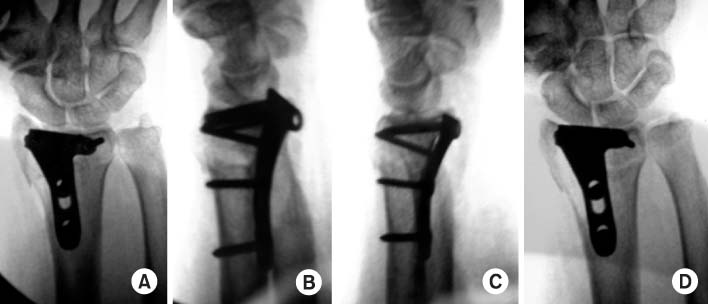

Fig. 11

(A) On anteroposterior view, plate and screws look like to violate the joint line.

(B) But they don't violate the joint on tilt view.

(C) At lateral view, it is not sure that the plate and scres involve the joint line.

(D) It can be confirmed that they don't violate the joint at radial tilt lateral view.

jkfs-21-325-g011.jpg

Fig. 11 (A) On anteroposterior view, plate and screws look like to violate the joint line. (B) But they don't violate the joint on tilt view. (C) At lateral view, it is not sure that the plate and scres involve the joint line. (D) It can be confirmed that they don't violate the joint at radial tilt lateral view.